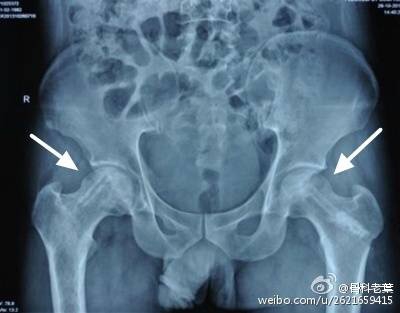

II期 病人有髋部症状,磁共振出现异常,X线片显示股骨头出现透光和硬化改变

III期 磁共振出现异常,X线片显示软骨下塌陷(新月征),股骨头内出现空洞,股骨头没有变扁

II期和III期的患者治疗方法相同,因为此时股骨头虽然还没有变形,暂时还不需要行人工关节置换术,但是股骨头已经出现空洞,随时股骨头就会塌陷变形,所以单纯的股骨头减压术是不能达到治疗效果的。这时就需要在股骨头减压的同时,植入一根支撑棒,顶住股骨头空洞区,防止股骨头在负重的情况下过早塌陷。其他治疗同之前相同,口服以上药物,定期复查,密切观察病情发展,尽量避免重体力劳动和爬山爬楼。

另附典型病例若干: